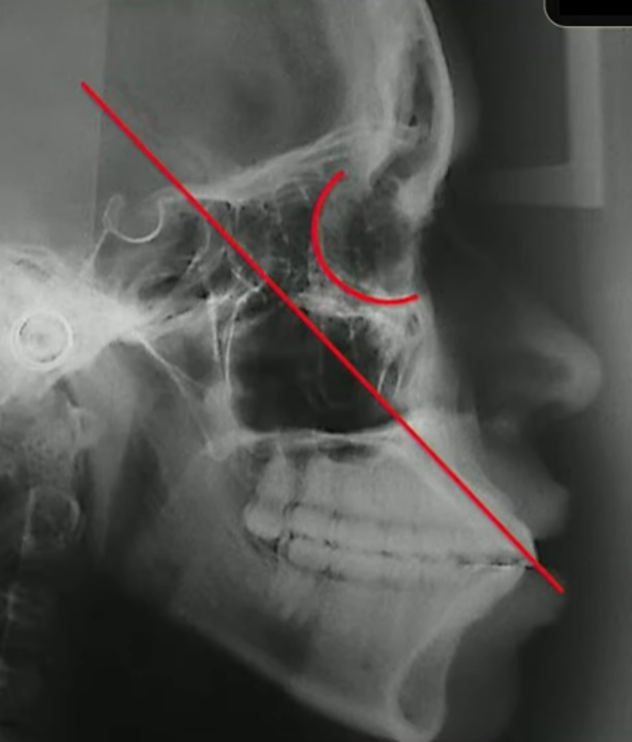

E aqui eu tiro a prova dos 9, eu tenho certeza absoluta que esse incisivo está vestibularizado porque eu tracei o longo eixo dele, ele passou muito atrás dessa órbita:

E eu também consigo traçar o meu incisivo inferior, medindo ele com a base mandibular:

Quando eu faço essa medida do incisivo inferior com a base mandibular, qual a minha intenção?

Eu quero saber também se esse incisivo inferior está mais ou menos com 90 graus em relação à base mandibular, nesse caso aqui eu tenho os incisivos bem vestibularizados.